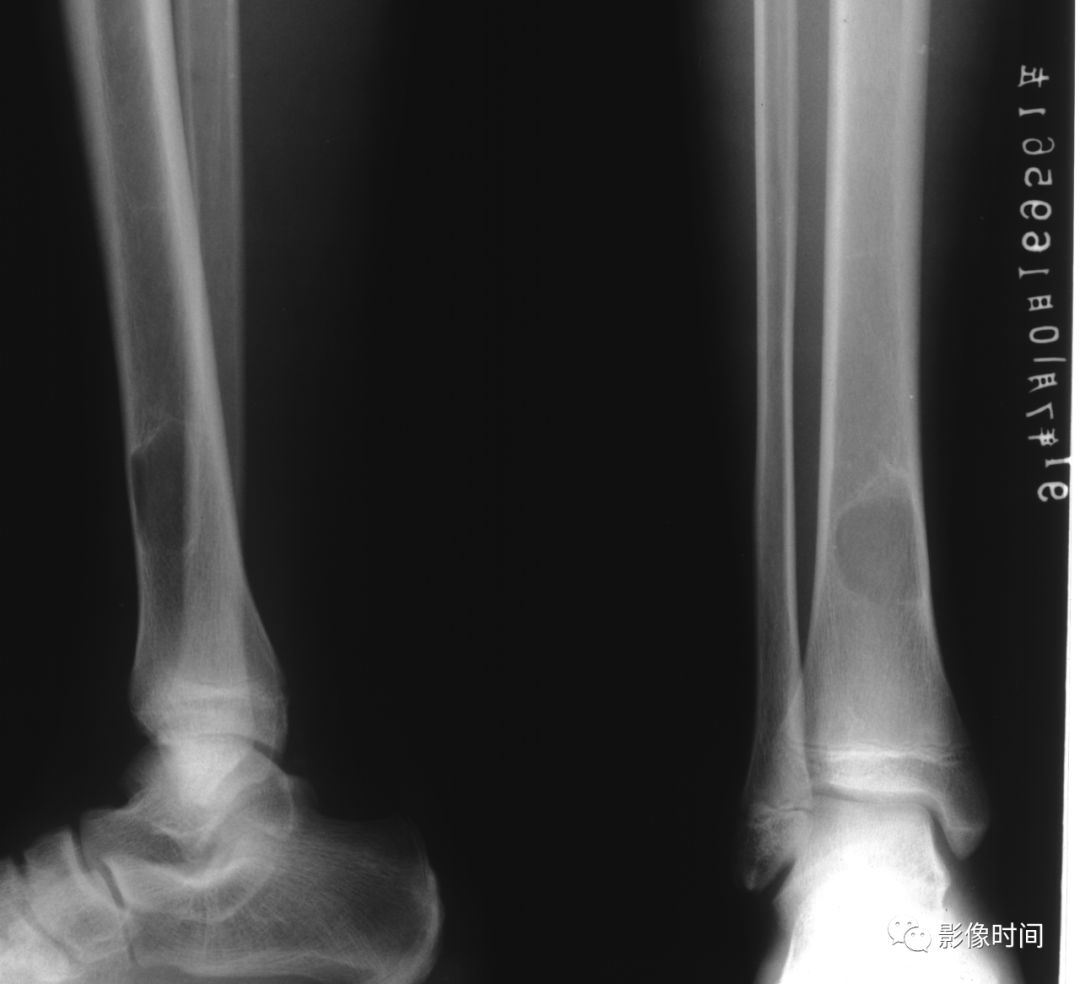

(一)地图样破坏  地图样破坏是指肿瘤组织在一个局部呈团块状生长造成界限清楚的骨质破坏(图 1、图 2、图 3、图 4)。

病灶可位于骨的中心或一侧部位,呈圆形、卵圆形密度减低区,与正常骨质分界清晰,边缘可有或无硬化带围绕,骨的形态无变化,病灶内可完全透亮或可见粗细不均、大小不等的残留骨嵴,内缘可光滑或呈分叶状压迹。

地图样破坏见于大多数良性肿瘤和肿瘤样病变如单纯性骨囊肿、骨纤维结构不良、血管瘤等、也可见于部分恶性骨肿瘤如骨转移瘤、骨髓瘤等。

图 1  地图样破坏:单纯性骨囊肿